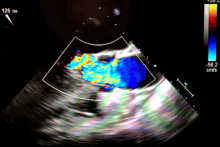

A 48-year-old woman presented with extreme shortness of breath that worsened on exertion. Transesophageal echocardiogram demonstrated marked concentric left ventricular hypertrophy and a resting left ventricular outflow tract gradient over 60 mm Hg. Systolic anterior motion of the mitral valve was absent. Cardiac magnetic resonance angiography showed papillary muscle hypertrophy and a left ventricular wall thickness of 2.8 cm.

Postoperative transesophageal echocardiography demonstrated a significantly enlarged left ventricle cavity with a peak gradient of 16 mm Hg. At six postoperative months, transthoracic echocardiography revealed a markedly dilated cavity and resolution of the intracavitary gradient. A combined approach prevents recurrence of elevated gradients and worsening symptoms from untreated midventricular obstruction [1, 2]. The Mayo Clinic has accumulated the largest series of patients with complex long-segment septal hypertrophy undergoing a combined approach. Their results are excellent, with low postoperative left ventricular outflow tract and midventricular gradients, low complication rates, short cross-clamp and perfusion times, and favorable short-term survival [1].